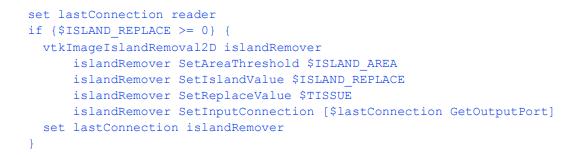

删除群岛

一些分割技术,特别是那些自动分割技术,可能会产生错误分类的体素岛。这个过滤器寻找带有ISLAND_REPLACE标签的连接像素,如果连接像素的数量小于ISLAND_AREA,它将它们替换为标签

组织。注意,这个过滤器只在ISLAND_REPLACE为正数时执行。